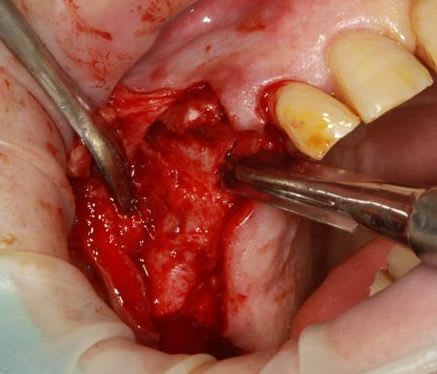

13 fenestration vestibulaire j'utilise la paroi palatine, lame N°15, spreader, expansion et pose d'un 40140

Ensuite zone 16 .. carottage, sciage en vest, carottage prélèvement de la carotte ajustage (délicat ça glisse:-)))